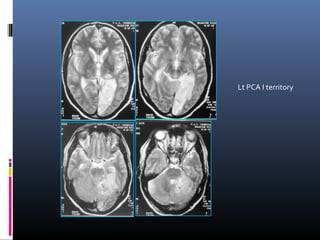

Lt PCA I territory

Lt PCA Iterritory